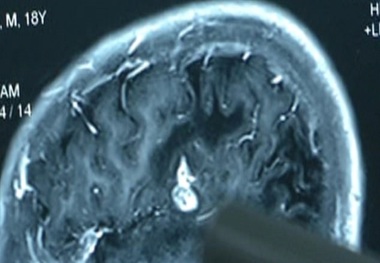

پیدا شدن انگلی 12 سانتی در سر فردی چینی!+ فیلم

انگلی 12 سانتی که به مدت 17 سال در سر مردی چینی زندگی می کرد توسط پزشکان خارج شد.